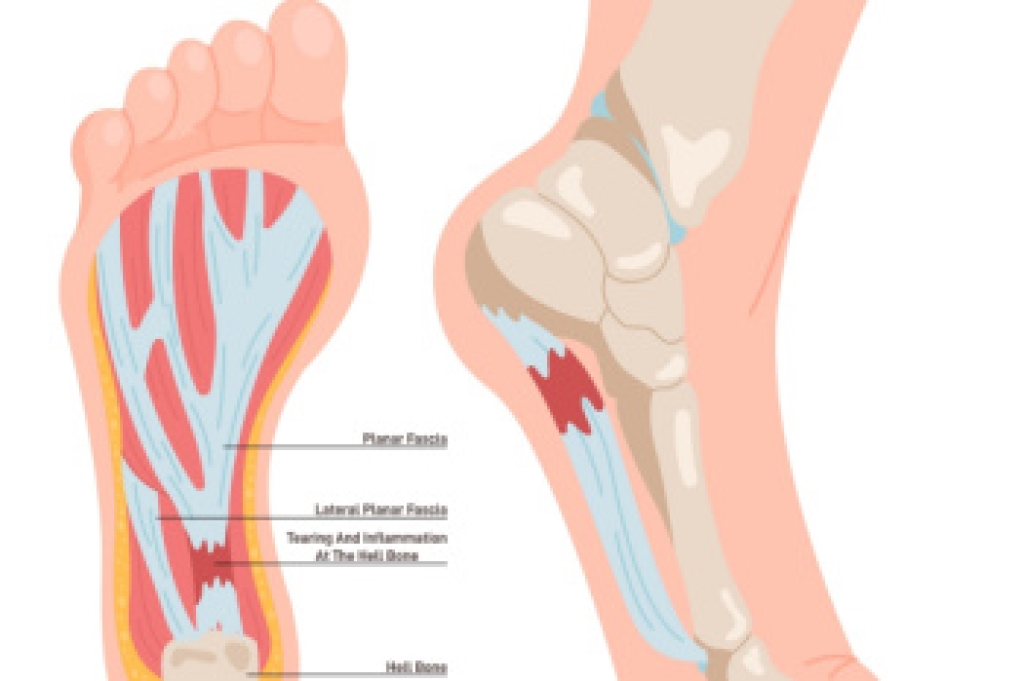

Heel spurs are bony growths that develop on the heel due to stress and inflammation in surrounding tissues. They are commonly seen in two forms. Heel spur syndrome affects the bottom of the heel, and insertional Achilles tendinitis affects the back of the heel where the tendon attaches. Risk factors include flat feet, high arches, excess weight, tight calf muscles, and repetitive impact activities. Symptoms may involve sharp heel pain, stiffness, and discomfort during the first steps of the day. A podiatrist can diagnose the condition, offer custom treatments, and provide guidance to relieve pain and improve function. If heel pain is limiting your daily life, it is suggested that you consult a podiatrist who can offer effective relief and treatment solutions.

Heel spurs are formed by calcium deposits on the back of the foot where the heel is. This can also be caused by small fragments of bone breaking off one section of the foot, attaching onto the back of the foot. Heel spurs can also be bone growth on the back of the foot and may grow in the direction of the arch of the foot.

Older individuals usually suffer from heel spurs and pain sometimes intensifies with age. One of the main condition's spurs are related to is plantar fasciitis.

The pain associated with spurs is often because of weight placed on the feet. When someone is walking, their entire weight is concentrated on the feet. Bone spurs then have the tendency to affect other bones and tissues around the foot. As the pain continues, the feet will become tender and sensitive over time.